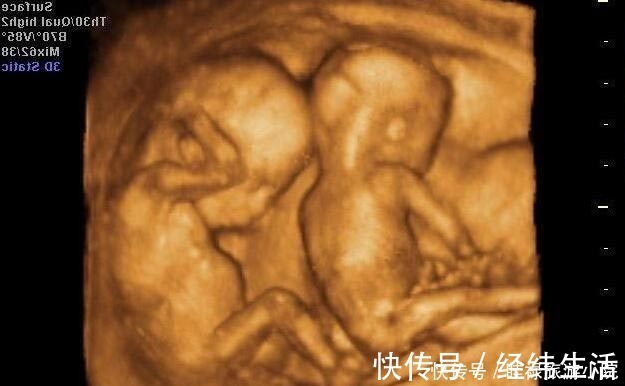

产检|孕期产检不想生个“傻孩子”,这三项产检必须按时做,不能忽视( 二 )

以上就是三个在孕期关于“胎儿智力”的检查,不少孕妈觉得自己都挺好的,会忽略产检,但其实每次产检都有意义也很重要,尤其这样的排挤检查,一定都要查查,别不当回事。关注「京妈说」,学习更多专业实用的母婴育儿知识,如果你喜欢这篇文章,要给京妈点赞并分享给更多的人。